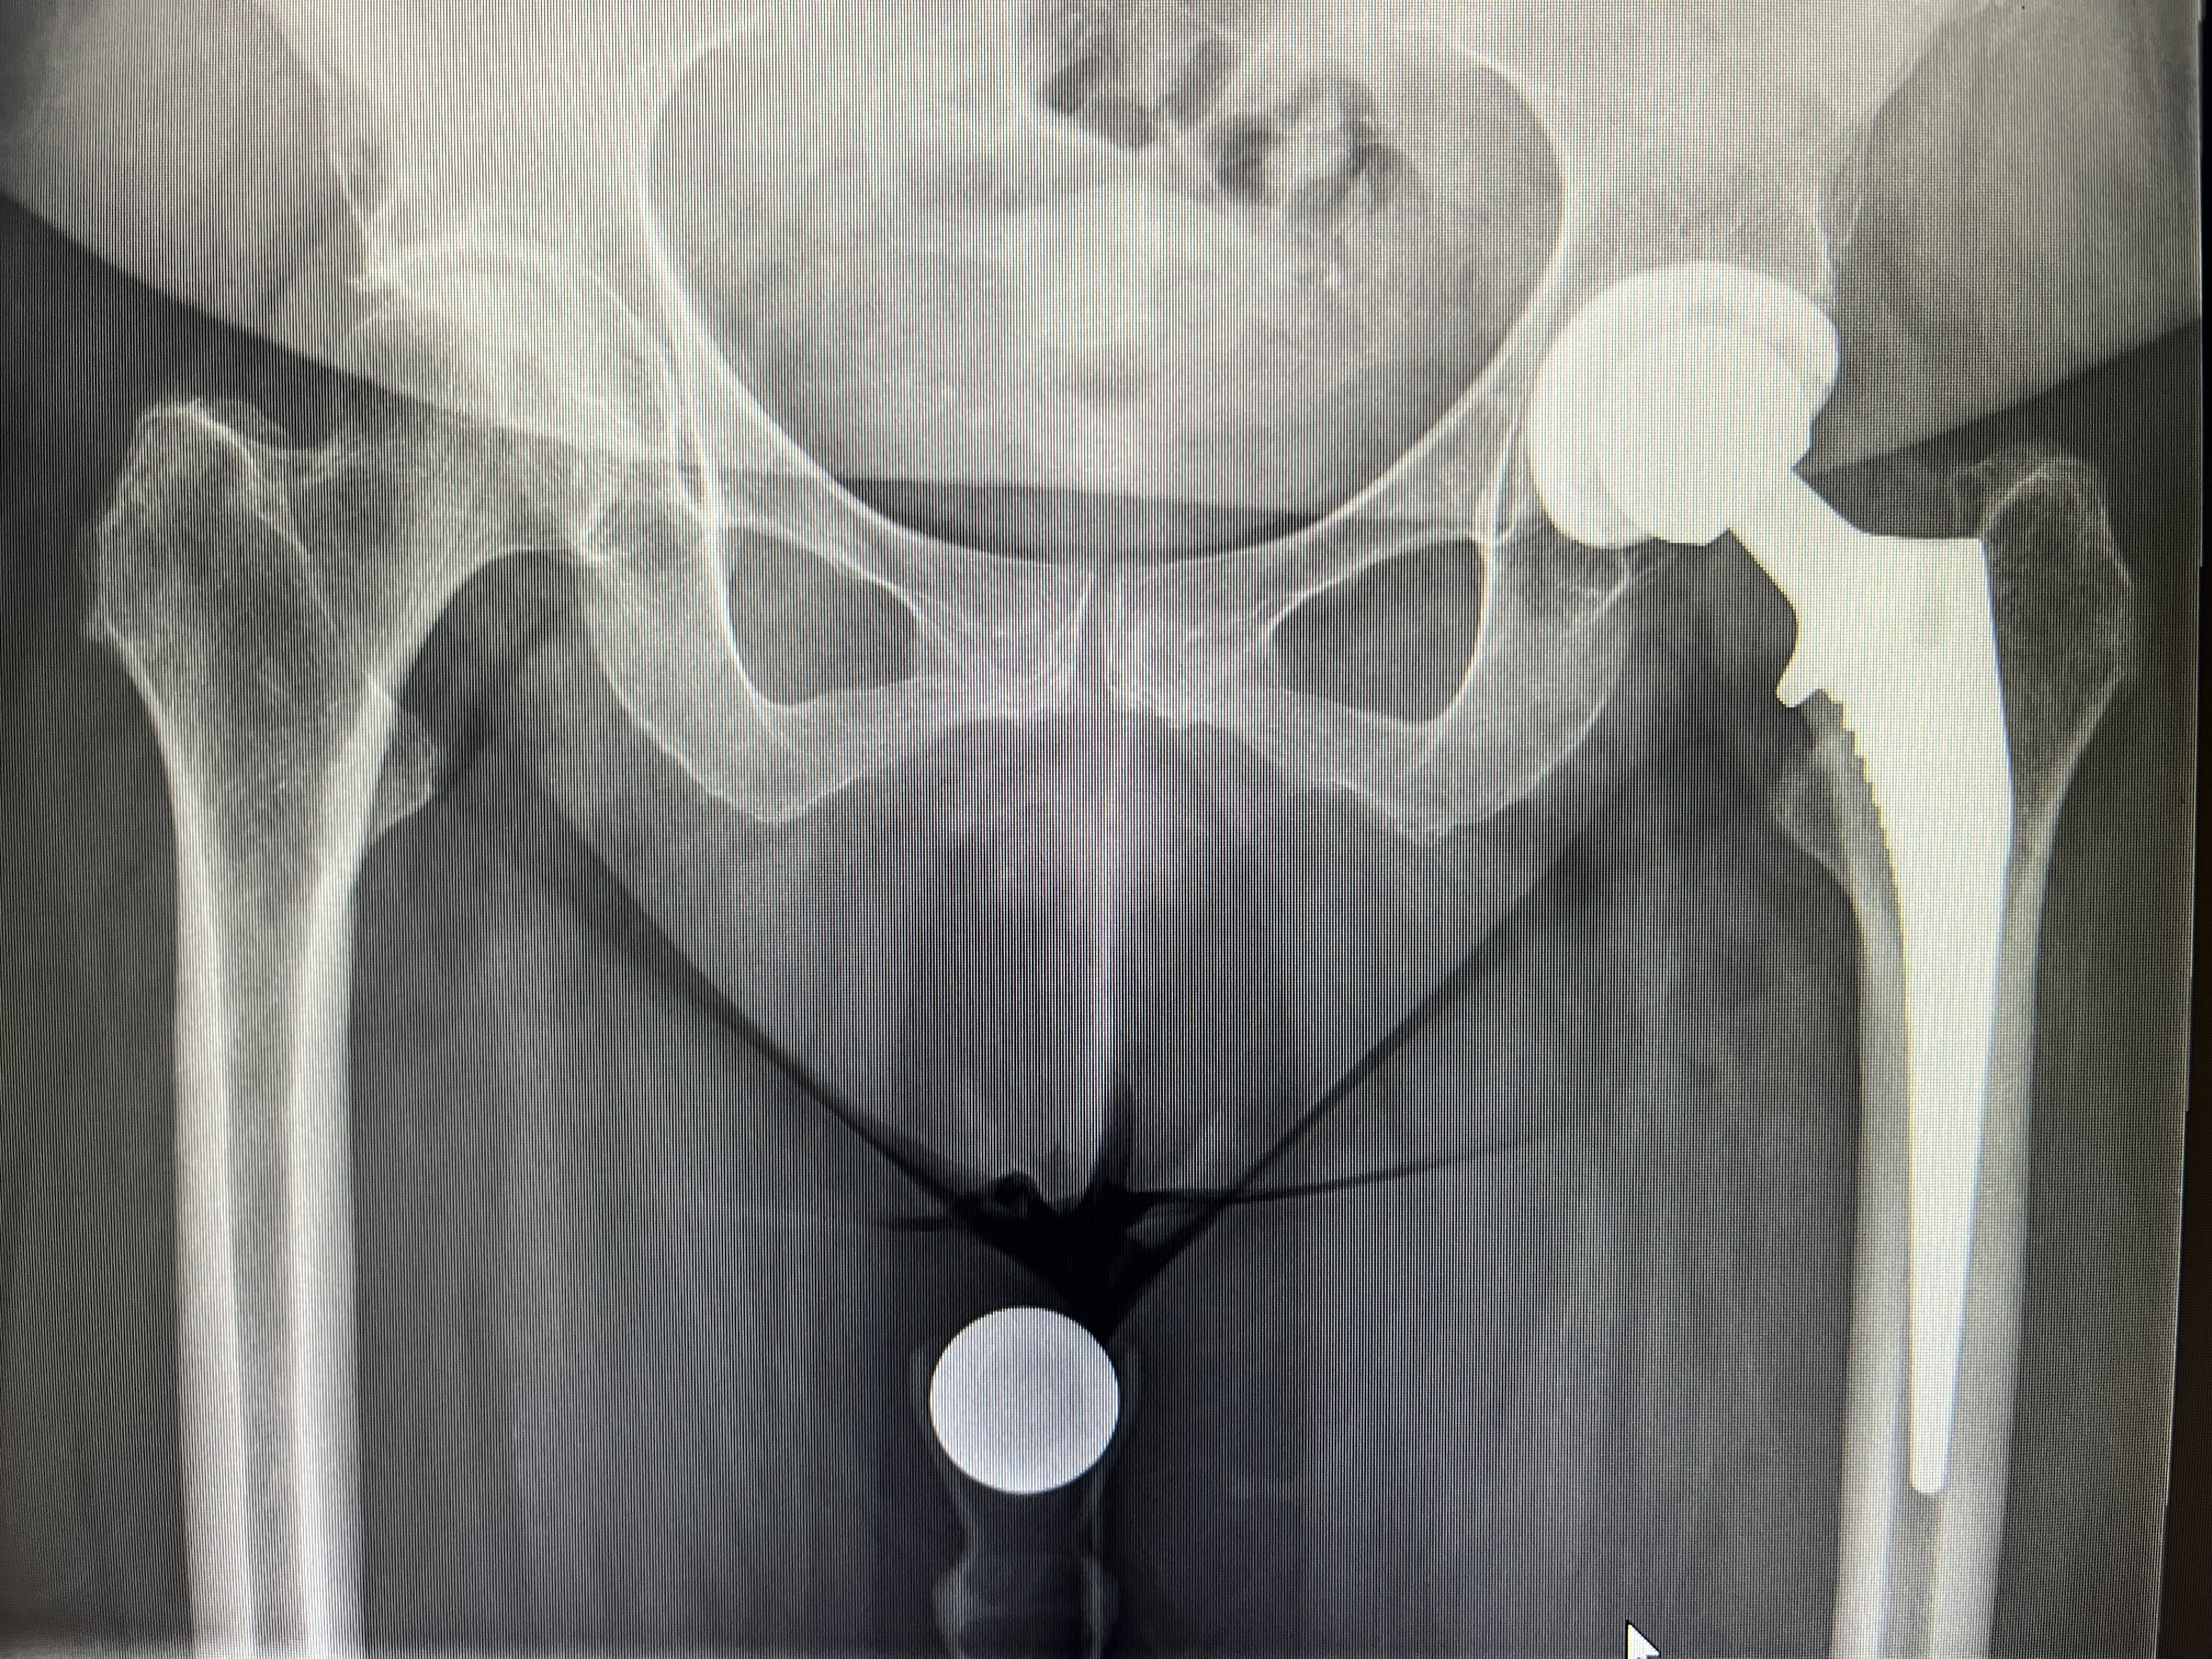

• Endoprothetik des Hüft- und Kniegelenkes